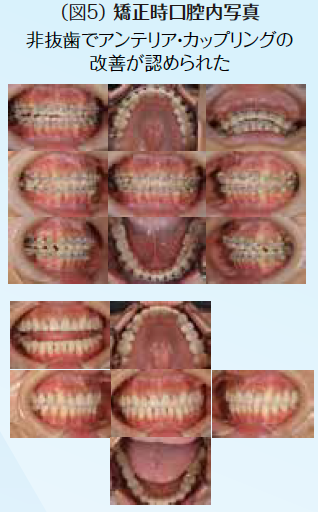

初期治療において炎症のコントロールを徹底するため、歯周治療と並行して、不良補綴装置を除去してプロビジョナル・レストレーションを装着し、感染根管歯は全て再治療を行なった。初期治療終了後、矯正治療を行なった。矯正学的診断が骨格性Ⅰ級で上下顎前突傾向があり、下顎前歯部の叢生によって犬歯関係はⅢ級関係を示していた。矯正治療を行うことで歯の位置関係が改善したことを確認したのち、確定外科をインプラント治療と合わせて行い、再評価の後に補綴処置を行なった。デジタル機器を用いることで機能的にも審美的にもまた患者の要求にも対応しやすくなった。補綴処置終了後再評価を行いメンテナンスに移行した。治療期間4年で術後4年近く経過したが、無髄歯の根尖周囲組織も有髄歯の歯髄の状態も良好に経過している。欠損部にインプラントを用いたことによってブリッジの支台歯になっていた無髄歯の予知性も向上したと考える。(図2〜図14)